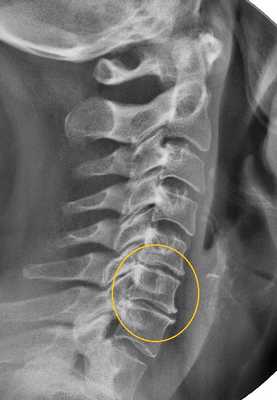

- рентгенография и компьютерная томография: эффективны лишь на поздних стадиях развития заболевания, когда изменения становятся хорошо заметными;

- магнитно-резонансная томография: благодаря высокой степени визуализации, позволяет видеть даже начальные изменения; в настоящее время является основным методом диагностики;